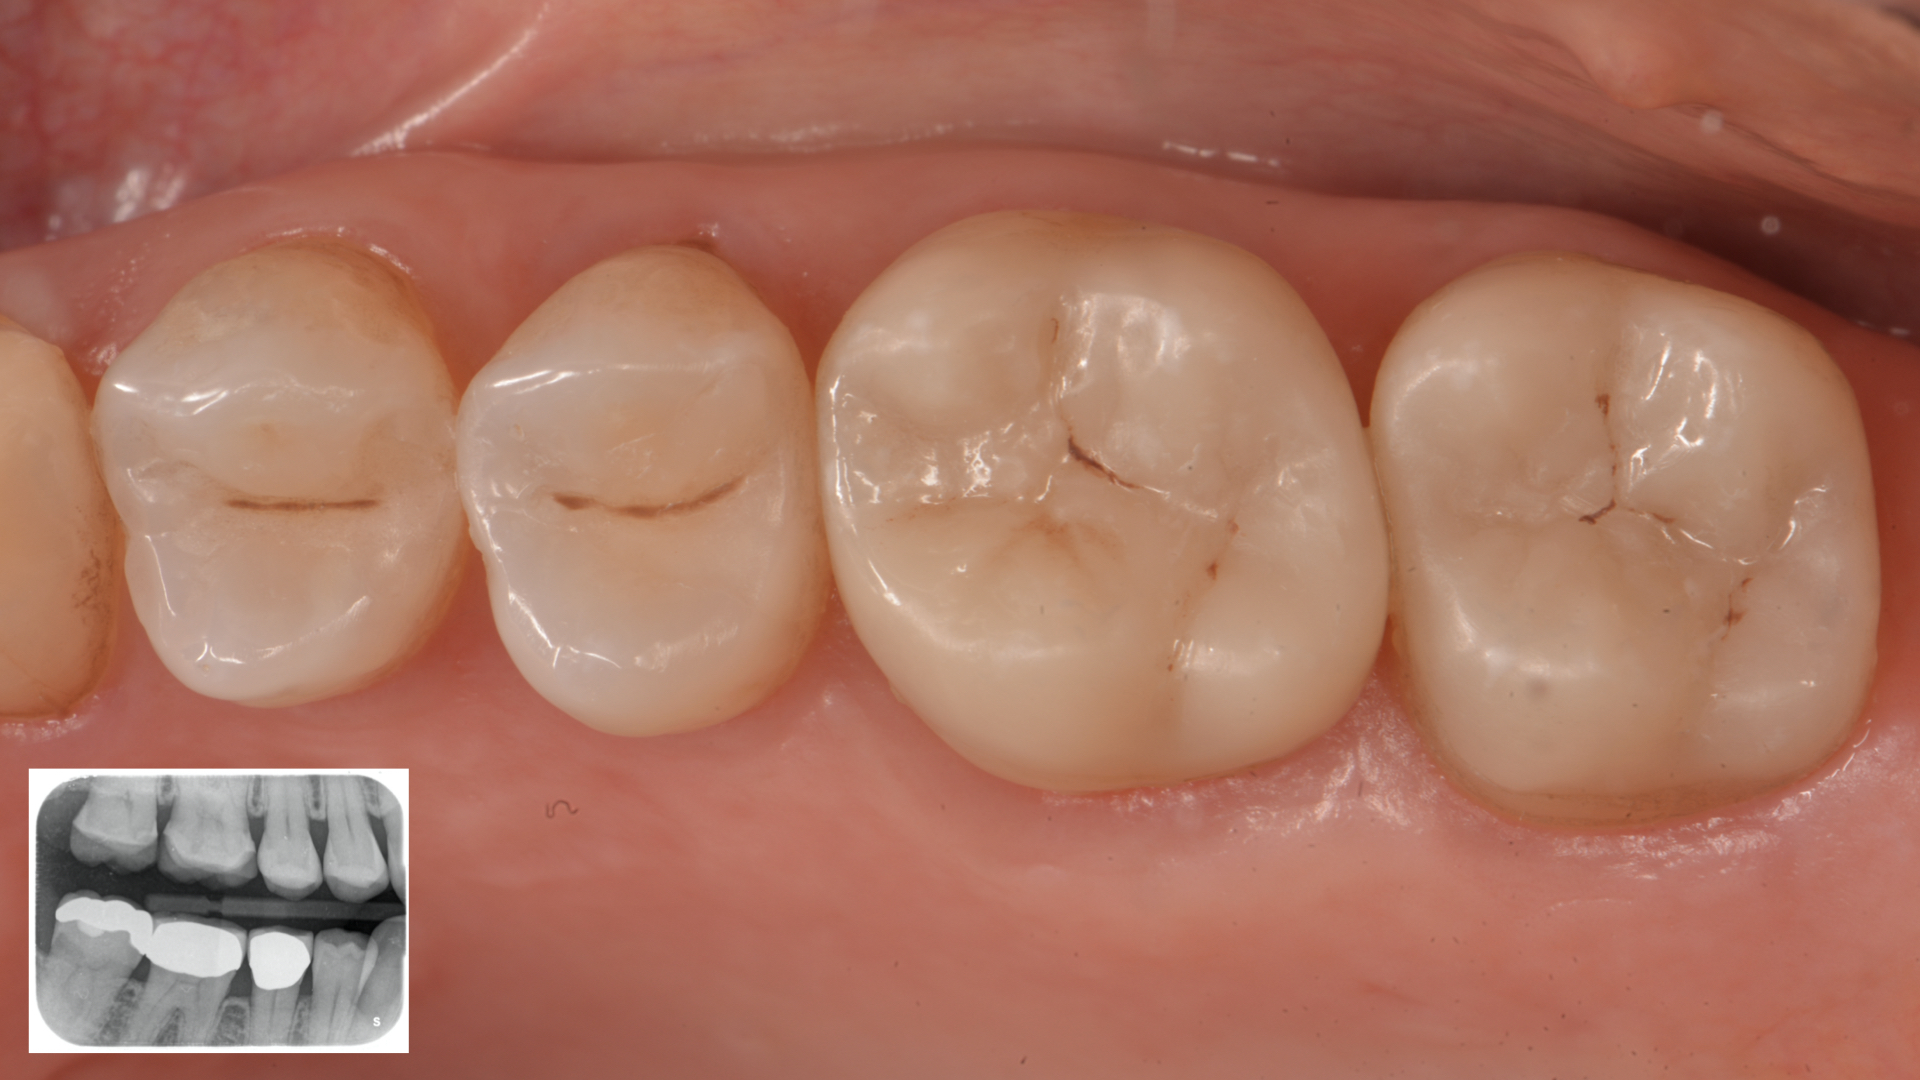

A patient came to our office, complaining about chewing and thermic discomfort in the upper right jaw. After clinical and radiographic examination, carious lesions on elements 1.7, 1.6, 1.5 and 1.4 have been detected. We chose direct restorations on teeth 1.4 and 1.5 with minimally invasive approach. On teeth 1.7 and 1.6 were instead selected indirect restorations (hybrid composite).

Figure 1. Preoperative situation. Occlusal view (Rx above)Figure 2. Isolation with rubber dam of the operative area